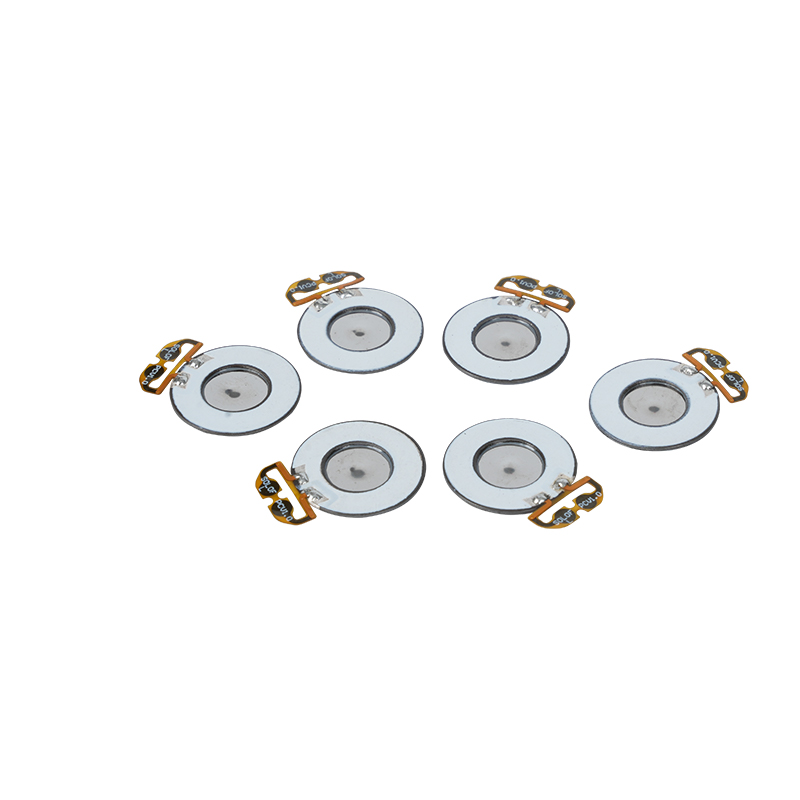

أقراص البخاخات الشبكية الطبية هي مكونات دقيقة تستخدم في الأجهزة الطبية لتحويل الأدوية أو المحاليل إلى جزيئات صغيرة من الهباء الجوي لعلاج اضطرابات الجهاز التنفسي المختلفة مثل الربو ومرض الانسداد الرئوي المزمن (COPD) وما إلى ذلك عن طريق الاستنشاق. يعد التصميم واختيار المواد لطبقة البخاخات أمرًا بالغ الأهمية لضمان توصيل الدواء بشكل فعال وراحة المريض. يتم ثقب ورقة الحجاب الحاجز غير القابل للصدأ بآلاف من الثقوب الشبكية الصغيرة مقاس 2-3 ميكرومتر في الصفائح الفولاذية من خلال تقنية الحفر بالليزر في عملية ليزر دقيقة، ومن ثم يتم ربطها بإحكام مع الصفائح المستديرة الخزفية الكهرضغطية، والتي تحول تردد الرنين للصفائح الكهرضغطية إلى طاقة اهتزاز عالية التردد من خلال إشارة الخرج للوحة تشغيل PCB، وتكسر بسرعة الدواء السائل إلى جزيئات الهباء الجوي الدقيقة. وتسمى هذه القطرات أيضًا بحجم الجسيمات المتوسطة، عندما تصل نسبة حجم الجسيمات المتوسطة D50 إلى> 60% أو أكثر، ستكون الجسيمات صغيرة بما يكفي لتتمكن من الوصول إلى عمق الرئتين إلى سطح الحويصلات الهوائية مع التنفس، وبالتالي تحسين كفاءة امتصاص الدواء والتأثير العلاجي. تحتوي صفائح البخاخات الشبكية الطبية الدقيقة بشكل أساسي على عدة أشكال، ورقة البخاخات الشبكية الدقيقة المصنوعة من الفولاذ المقاوم للصدأ، ورقة البخاخات الطبية بالنيكل والبلاديوم، ورقة البخاخات الطبية بوليمر PI، وما إلى ذلك. كل ما سبق يتم من خلال تحويل طاقة الاهتزاز الخزفي الكهرضغطي لتحقيق تأثير الانحلال.

بوليميد (بوليميد) يشار إليه باسم PI، هو أفضل أداء شامل لمواد البوليمر العضوية، وله ثبات كيميائي ممتاز، ويمكنه تحمل التآكل الناتج عن مجموعة متنوعة من الأدوية، لضمان الاستخدام طويل الأمد لأداء الأقراص المذرية. بالإضافة إلى ذلك، فإن الثبات الحراري لفيلم البوليمر PI ممتاز أيضًا، مع الاستخدام طويل الأمد لنطاق درجة الحرارة -200 ~ 300 درجة مئوية، والعزل العالي، وحماية البيئة، وغير السمية، كمواد هندسية خاصة، تستخدم على نطاق واسع في أغشية الفصل البلوري السائل النانوي للإلكترونيات الدقيقة وغيرها من المجالات، وقد تم تضمينها في القرن الحادي والعشرين من قبل بلدان واحدة من أكثر المواد الهندسية الواعدة، وليس من السهل أن تكون مشوه أثناء عملية التطهير بدرجة الحرارة العالية، لضمان إعادة استخدام المنتج! من أجل الجنس والسلامة، نستخدم تقنية الليزر لثقب الليزر، وفيلم PI مزروع بين الفولاذ المقاوم للصدأ والصفائح الكهرضغطية، واستخدام تقنية الموجات فوق الصوتية الخزفية الكهرضغطية بحيث تتوزع القطرات المتناثرة من خلال فيلم PI إلى ذرات من جزيئات 3 ~ 4 ميكرومتر لاستنشاق البخاخات الطبية، وهي سلامة غالبية المستخدمين الذين يحبونها، مصنوعة من البخاخات مع الميزة الرئيسية لـ PI هي عدم الانسداد، والجدار الداخلي للفتحة أملس ومستدير، ولا يوجد بقايا للسائل، والانحلال دقيق ومستقر. الانحلال دقيق ومستقر. أقراص البخاخات ذات الفيلم PI يمكنها أن تمنع بشكل فعال بقايا الأدوية، وتقلل من خطر التلوث المتبادل. في التطبيق العملي، انعكست أيضًا خصائص استهلاك الطاقة المنخفضة لأقراص البخاخات ذات غشاء البوليمر PI، باختصار، أصبحت أقراص البخاخات ذات غشاء البوليمر PI مع أدائها الممتاز ومزايا التصميم، جزءًا لا غنى عنه في مجال علاج البخاخات الطبية.

يُعرف السيراميك الكهرضغطي الخالي من الرصاص باسم "لؤلؤة" صناعة الكهرضغطية، وسيحل المستقبل تدريجيًا محل السيراميك الكهرضغطي القائم على الرصاص في جميع الجوانب، والذي يتمتع بالفعل بنفس الأداء الكهرضغطي، والصفائح الكهرضغطية القائمة على الرصاص. إنها غير سامة تمامًا وغير ضارة وآمنة وصديقة للبيئة، ولا تحتوي على الرصاص والأنتيمون والمعادن الثقيلة الأخرى وغيرها من العناصر المقيدة بـ Rohs، درجة حرارة كوري عالية Tc-328 درجة مئوية، وفقدان كهربائي منخفض جدًا TangentLoss ولذلك، فإن رقاقة الانحلال الطبي الكهرضغطية الخالية من الرصاص لها قيمة تجارية كبيرة وقيمة عالمية، والسيراميك الكهرضغطي غير سام وصديق للبيئة وخالي من الرصاص بالإضافة إلى الأداء غير الملوث والكهرضغطي الذي يتناسب مع السيراميك القائم على الرصاص، سوف يصبح سيراميك كهرضغطية صديق للبيئة مشهورًا. بعد سنوات من البحث والتطوير، وبعد الاختبار المستمر والتجربة، نجحت الشركة في صنع شريحة الانحلال الطبي الخالية من الرصاص لتحقيق نفس كمية الانحلال مثل شريحة الانحلال المعتمدة على الرصاص، ونفس متطلبات جسيمات القطر. شريحة البخاخات الشبكية الطبية الخالية من الرصاص، سوف تتألق بالتأكيد وستحصل على مجموعة واسعة من سيناريوهات الاستخدام.